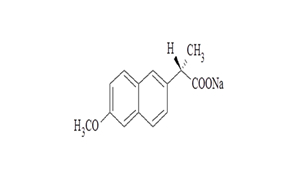

Naproxen Tablets USP

| 250 mg | Tablet | Rx | Naprosyn |  | 62207-745-43 62207-745-47 62207-745-49 |

Medication Guide |

| 375 mg | Tablet | Rx | Naprosyn |  | 62207-746-43 62207-746-47 62207-746-49 |

Medication Guide |

| 500 mg | Tablet | Rx | Naprosyn |  | 62207-747-43 62207-747-47 62207-747-49 |

Medication Guide |